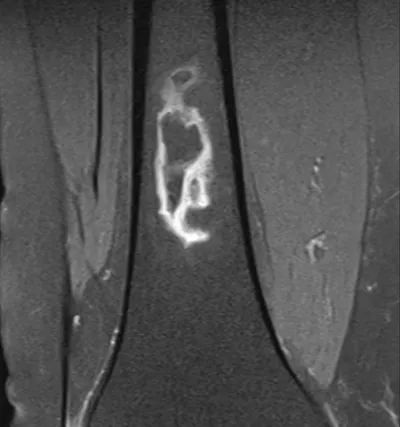

Infarct Radiology Images

Browse 2 medical images tagged with infarct. This collection includes various imaging modalities for medical education and reference.

About Infarct Imaging

This collection contains 2 radiology images related to infarct, including various imaging modalities such as X-rays, MRIs, CT scans, and ultrasound images commonly used in medical diagnosis and education.